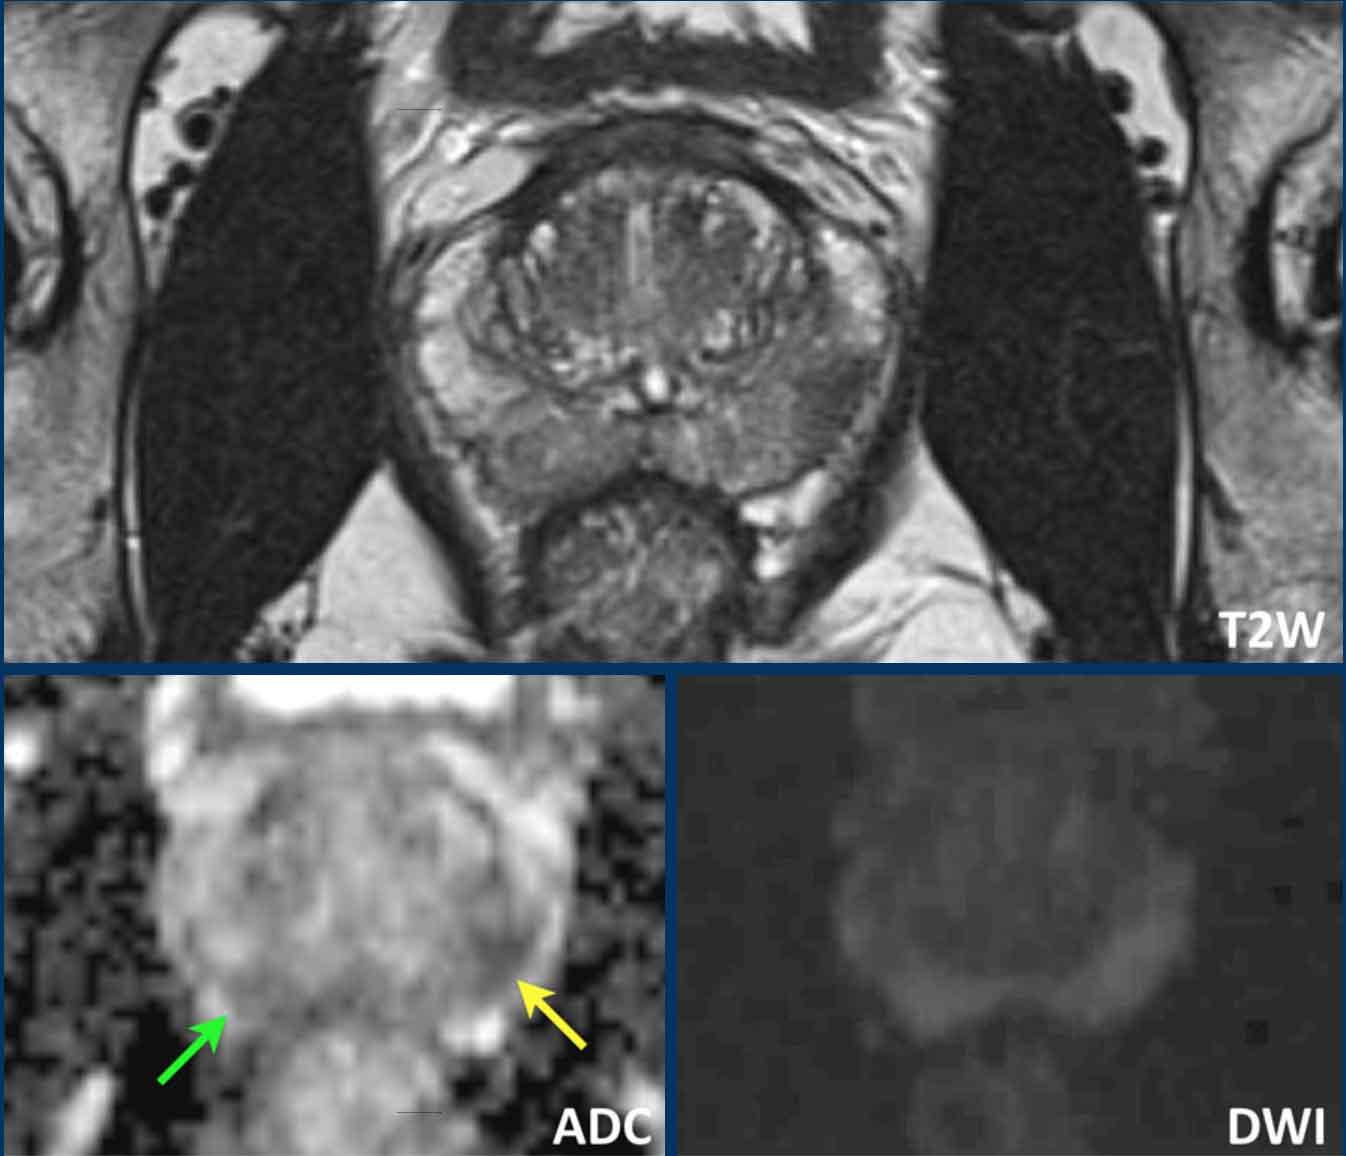

Hãy quan sát hình ảnh trước rồi tiếp tục đọc.

Các phát hiện bao gồm:

- Một tổn thương kích thước 17 mm (không hiển thị phép đo) nằm ở vùng ngoại vi, phía sau bên trái của phần giữa tuyến tiền liệt.

- Giảm tín hiệu rõ rệt trên ADC và tăng tín hiệu rõ rệt trên DWI.

- Tương ứng với vùng giảm tín hiệu trên chuỗi xung T2W.

- Trên chuỗi xung T2W, tổn thương tiếp xúc diện rộng với vỏ bao tuyến tiền liệt.

Tổn thương này được xếp vào phân loại PI-RADS 5 với nghi ngờ xâm lấn ra ngoài tuyến tiền liệt.

Điểm Gleason là 4+3.

Tổn thương nghi ngờ này có hạn chế khuếch tán đáng kể.

Giá trị ADC đo được là 440 mm²/s.

Giá trị ADC thấp cho thấy nguy cơ ác tính cao hơn.

Giá trị ADC thực tế có tương quan nghịch với khả năng ác tính có ý nghĩa lâm sàng.

Các giá trị trên 900 mm²/s được coi là có khả năng lành tính và dưới 750 mm²/s có khả năng ác tính.

Tuy nhiên, kết quả định lượng có thể khác nhau đáng kể giữa các máy chụp và các giao thức chụp.